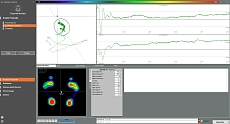

Интегрированное программное обеспечениеFreestep

- Высокая скорость сбора данных

- Автоматические отчеты

- Пространрственно-временные параметры

- Синхронизация видео